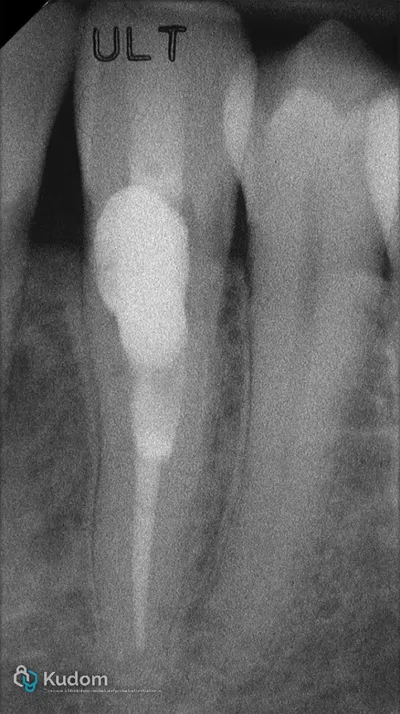

Ritrattamento endodontico complesso di un primo molare inferiore con lesione alla forcazione e otturazione di un canale laterale con successivo build-up per overlay a ricopertura cuspidale.